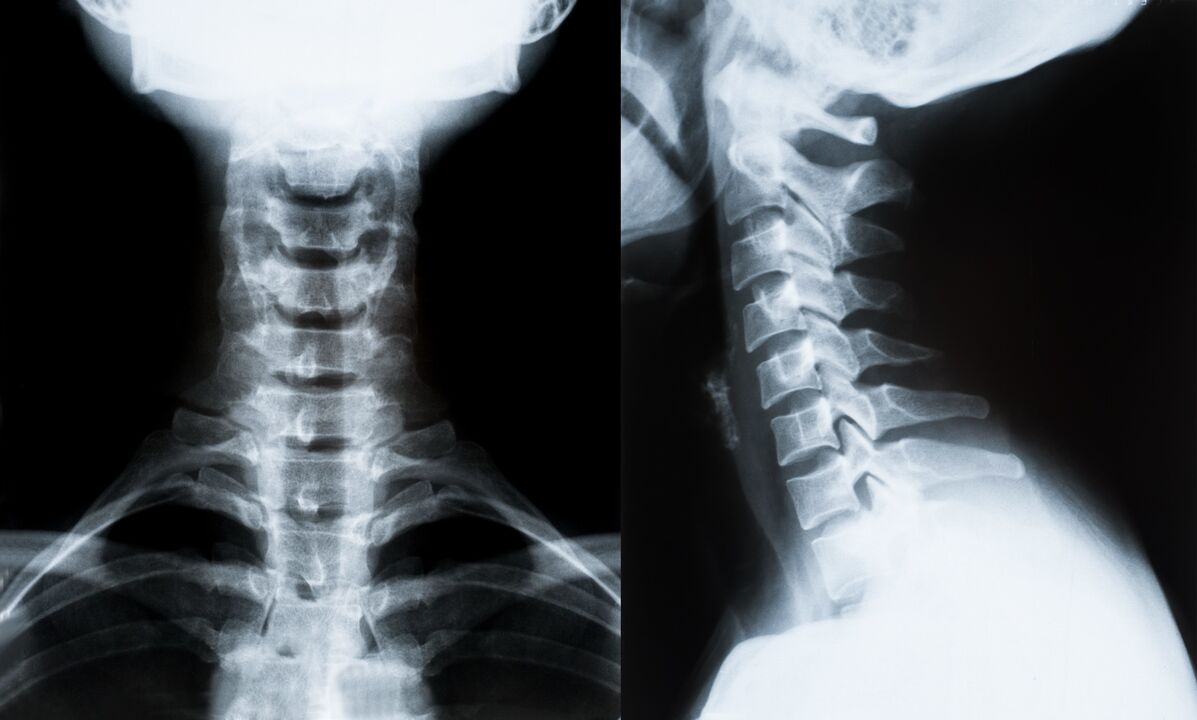

Pagrindiniai kaklo stuburo osteochondrozės diagnozavimo ir tolesnio gydymo nustatymo metodai:

- Rentgenas. Mažiausiai veiksmingas, bet tradicinis diagnostikos metodas.

- Magnetinio rezonanso tomografija yra efektyviausias diagnostikos metodas. Atliekant tokio tipo paciento tyrimą, matomos visos reikalingos struktūros.

- Jei reikia išmatuoti pakitimus, naudojama kompiuterinė tomografija. Nustato išvaržų ir kitų dalykų buvimą.

- Paskutinis metodas yra ultragarsinis dvipusis skenavimas. Šiuo tyrimo metodu nustatomas kraujo tėkmės greitis arterijose.

Namuose neįmanoma tiksliai nustatyti stuburo ligos.